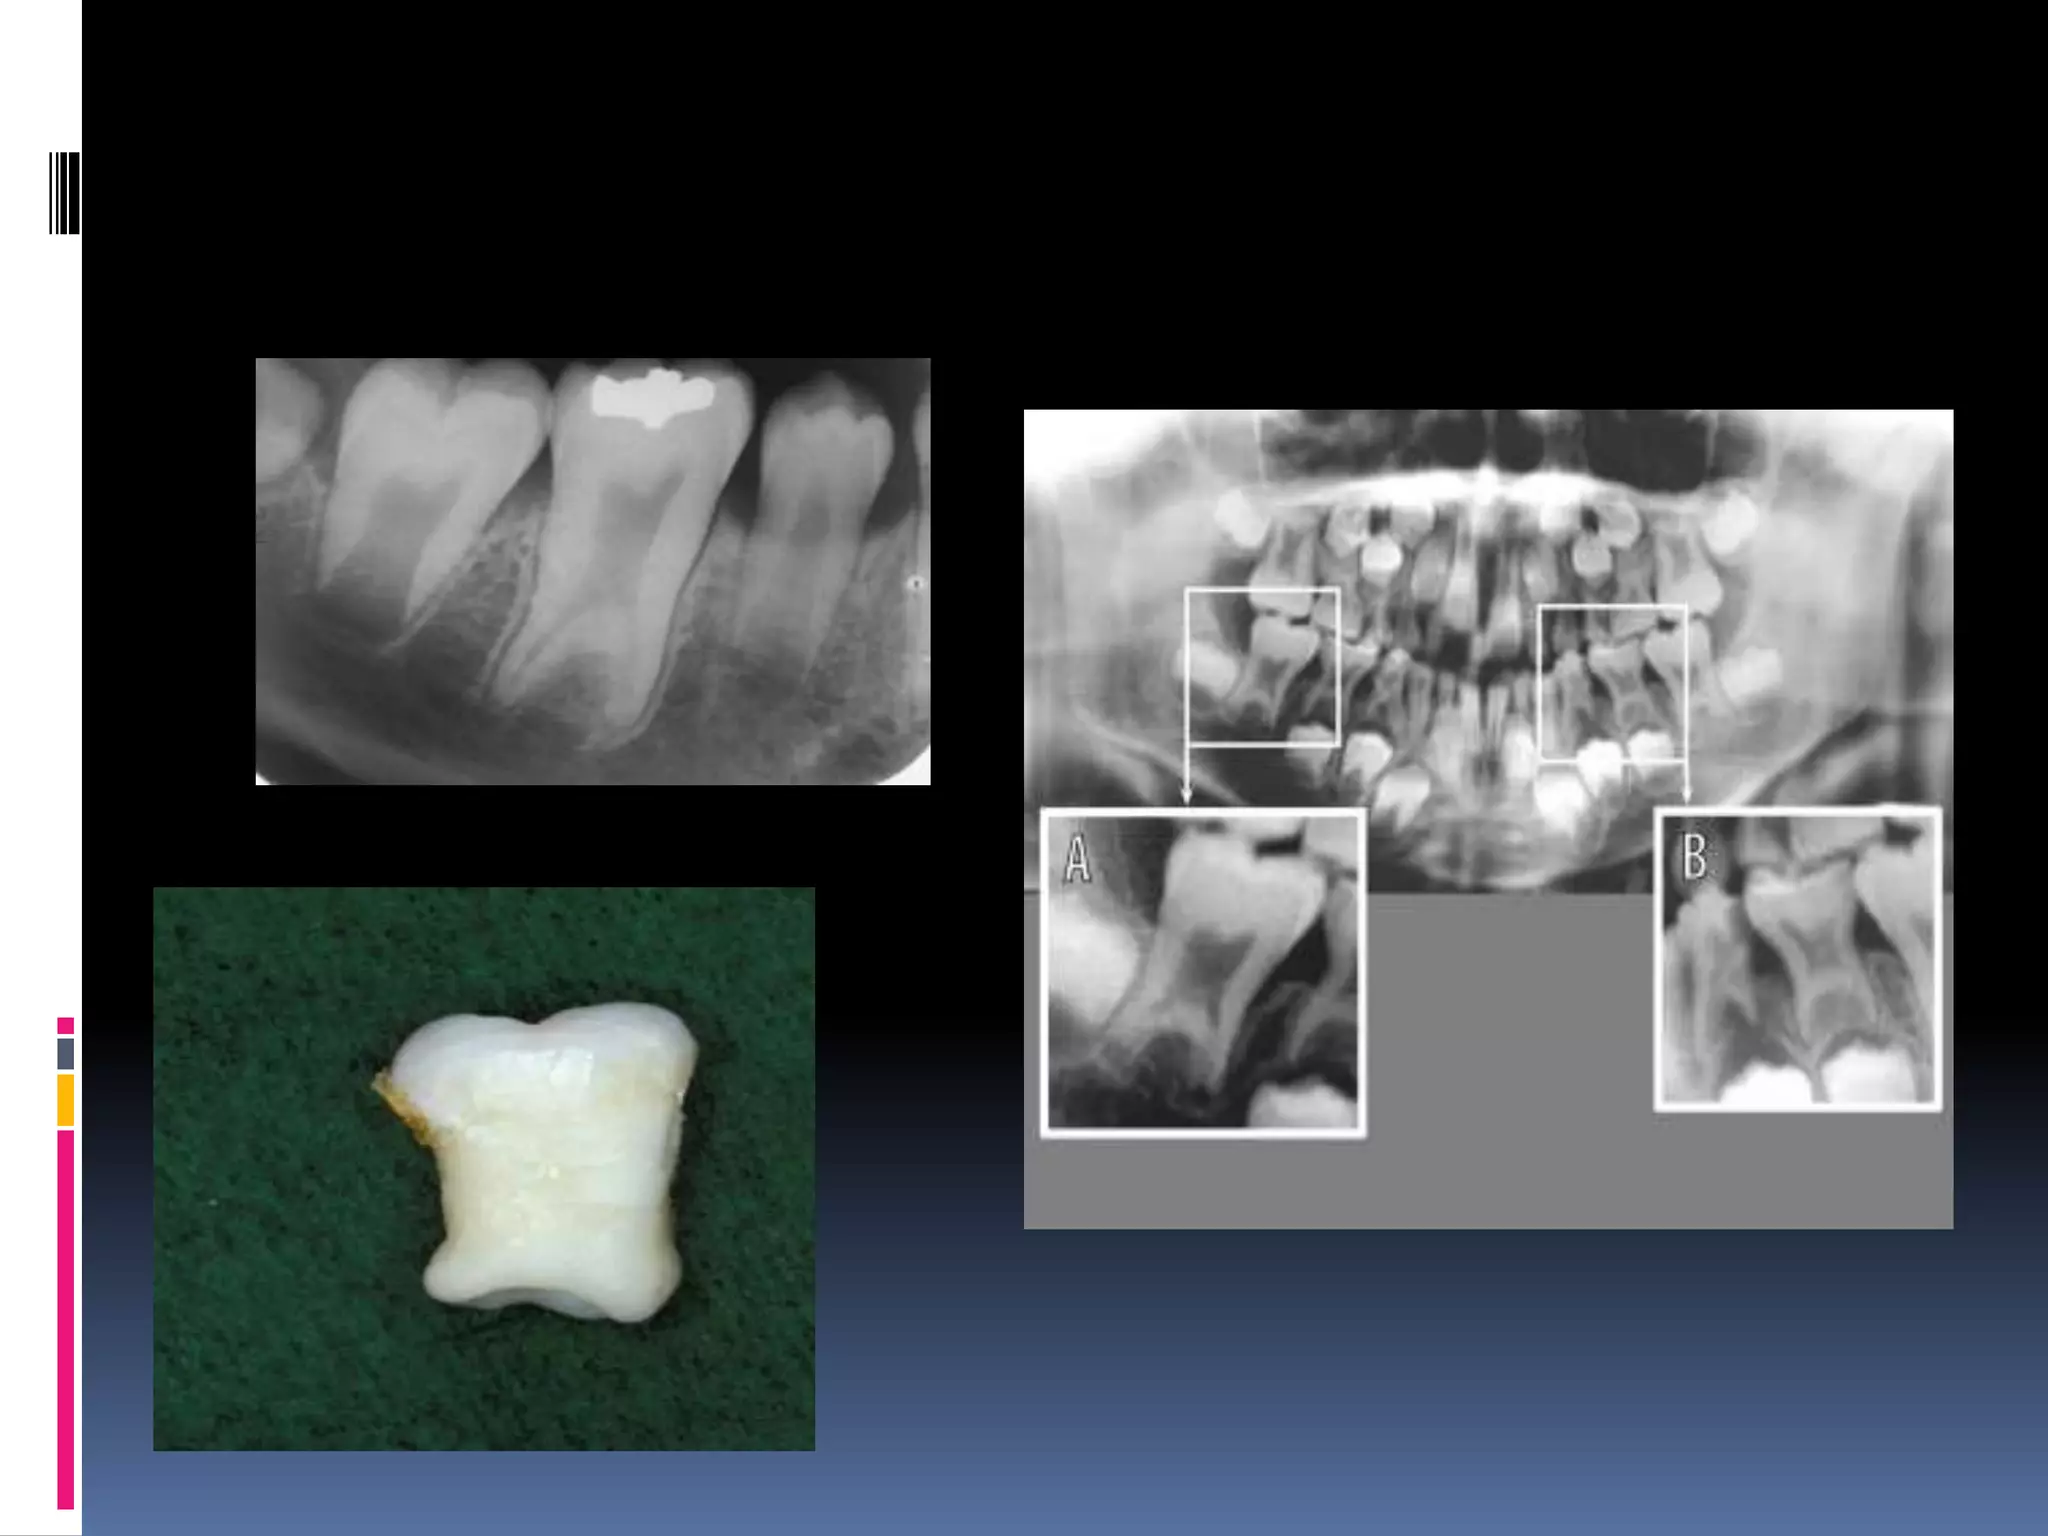

Ectopic enamel

 Presence of enamel in unusual locations.

i)Enamel pearl /enameloma:

Hemispheric structures consist entirly of

enamel/ contain dentin & pulp.

 Due to prolonged contact b/t hertwig’s root

sheath & developing dentin inducing enamel

formation.

 1-4 epithelial pearls.

> in root furcation /near CEJ.

 R/F – well defined radiopaque nodules along

root surface.(CEJ)

Hypercementosis/cemental

hyperplasia

 Non neoplastic deposition of excessive

cementum continuous with normal

radicular cementum

 Generalised - paget’s

Disease

 isolated

radiology

thickening/

blunting of root

root outline is enlarged &

delineated by PDL

space & lamina

dura

 hypercementosis



 condensing osteitis

Bulbous root

 Increased dentin

 Widened root apex